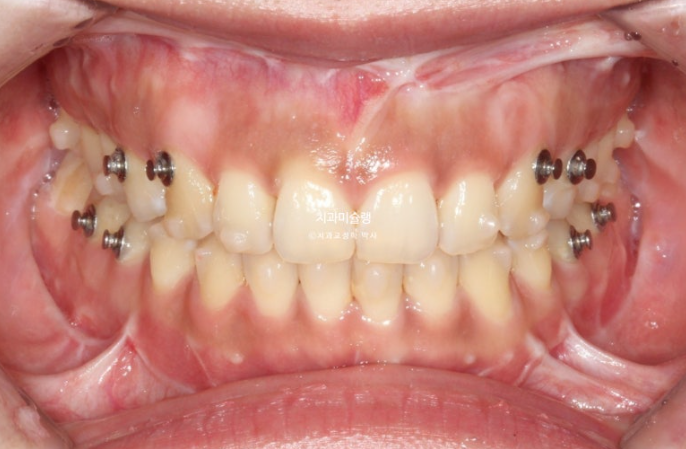

선수술 후 한달간의 회복기를 거쳐 25년 1월 본원에 내원했을 때의 교합 상태입니다.

25.01

아래 앞니 하나에 변색이 보입니다.

앞니 두 개는 나비치아 돌출이며

어금니 교합이 떠있습니다.

앞니에 배열이 삐뚤합니다.